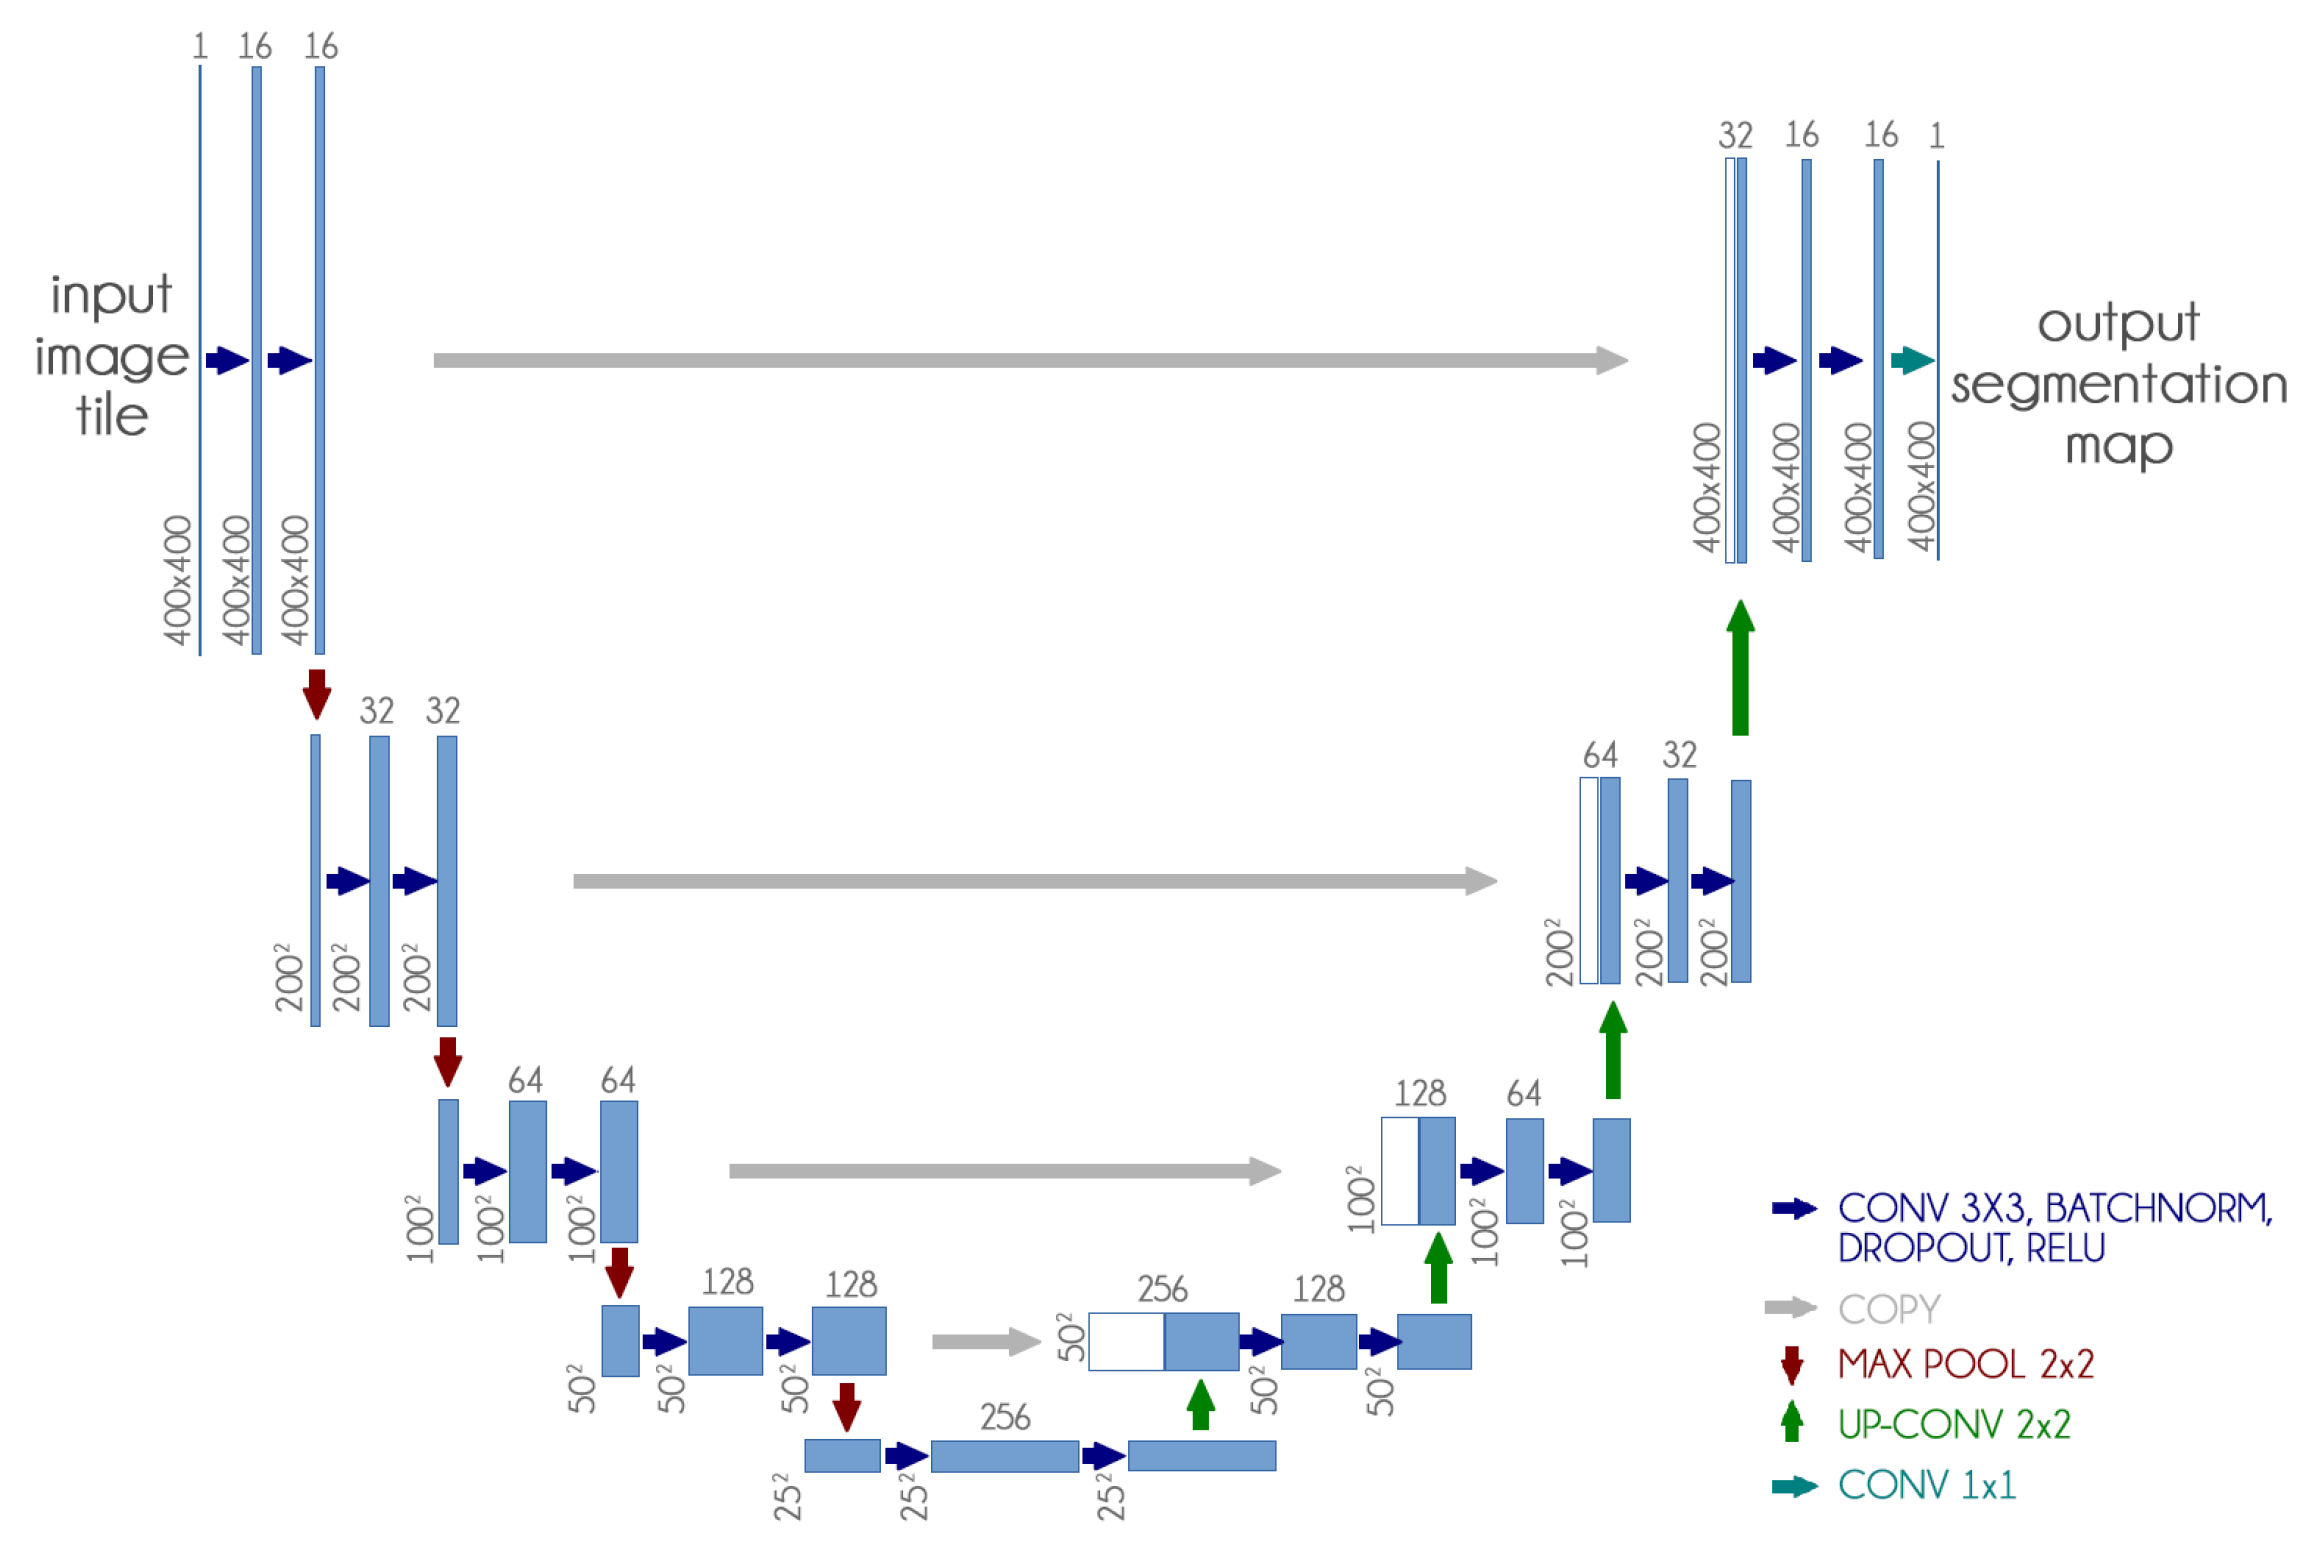

3.1.2. U-Net

The U-Net CNN architecture is a fully convolutional network (FCN) that has two main components: a contraction path, also called an encoder, which captures the image information; and the expansion path, also called decoder, which uses the encoded information to create the segmentation output [

13].

We used the U-Net CNN architecture with some small changes: we included dropout and batch normalization layers in each contracting and expanding block. These additions aim to improve training time and reduce overfitting.

Figure 4 presents our adapted U-Net architecture.

Furthermore, since our dataset is not standardized, the first step was to resize all images to 400 px × 400 px, because it presented a good balance between computational requirements and classification performance. We also experimented with smaller and larger dimensions with no significant improvement.

In this model, we achieve a much better result without using transfer learning and training the network weights from scratch.